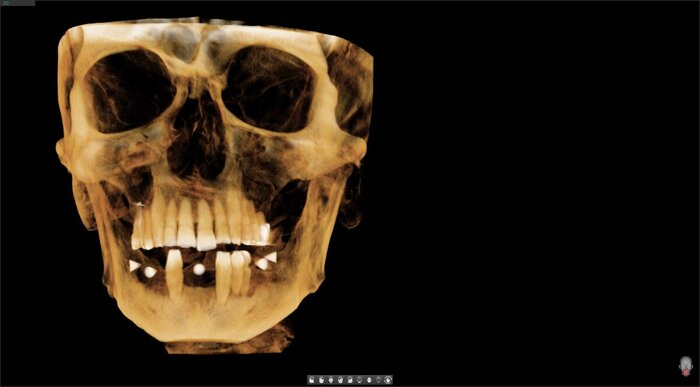

КЛКТ

Да и смысл добавлять скан - всё видно и понятно. На нижней челюсти 4 зуба, которые никуда не годятся.

Справа - одинокий воин.

Слева - компания друзей навынос.

Белые точки на нижней челюсти - маячки.

Для чего это нужно? Доктору необходимо провести имплантацию в цифре - подобрать оптимальное расположение зубов (протеза), к этому положению подобрать оптимальные имплантаты - по диаметру, по длине, по расположению в кости. Для этого Егор Романович "склеивает" в специальной программе данные рентгена (КЛКТ) и цифровой слепок (3Д скан). Так как зубов нет почти, то нет и ориентиров - программа не может соединить корректно одно с другим. Мы не видим границу зубов предполагаемых. Вот и создаём ориентиры самостоятельно.

Сделали КЛКТ: